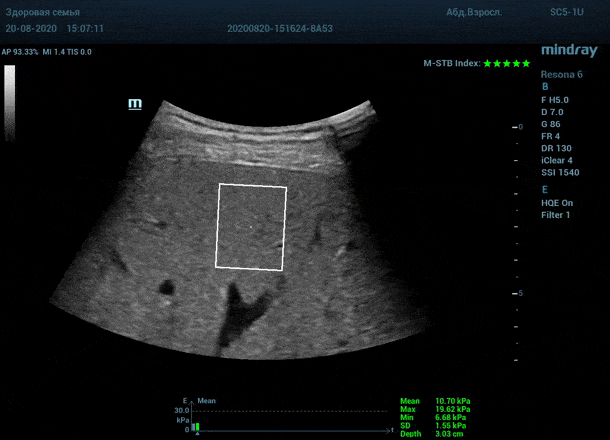

Как работает эластография сдвиговой волны? Датчик посылает плотный пучок ультразвуковых волн в ткани, ткани сжимаются, а затем возвращаются в исходное состояние за счет своей эластичности. Расправление ткани создают поперечные ультразвуковые волны, которые регистрируются трансдьюссером. Прибор во время исследования непрерывно отображает график значений плотности печени (kPa) в исследуемой зоне, достоверным считается график в виде прямой линии. Такая линия формируется путем получения близких по значению показателей. Количественным показателем является отношение межквартального интервала к медиане (IQR/Med). Допустимым считается результат с IQR/Med менее 30%. Чем данный показатель меньше, тем более точным является исследование. Для достоверного исследования в идеале нужно 10 значений.

- - Неподвижная печень. Достигается путем задержки дыхания на выдохе. Выдох позволяет уменьшить давление на печень органами грудной клетки и брюшной полости. Задержка дыхания останавливает её. Критерием качества является индекс M-STB, выраженным в количестве звезд. Прибор определяет его автоматически. 4-5 звезд индекса свидетельствует о неподвижной печени.

Для таких сложных случаев в приборах Mindray Resona предусмотрен режим HQ Elasto. В отличии от стандартной работы эластографии HQ Elasto позволяет собрать отдельное короткое измерение в сборный график. Достаточно задержки дыхания всего в пару секунд, показатель будет записан и добавлен в график измерений. Таким образом, короткими «залпами» ультразвуковых волн по печени доктор без проблем соберет все необходимые 10 значений и проведет автоматический анализ с расчетом медианы и IQR/Med.

Приводим видео пример: использованы 3 точки доступа печени, каждое значение графика получено прицельным выстрелом HQ Elasto и собрано в единый тренд. В результате анализа 10 значений получен удивительно точный результат - статистический разброс 3.5 % IQR/Med.